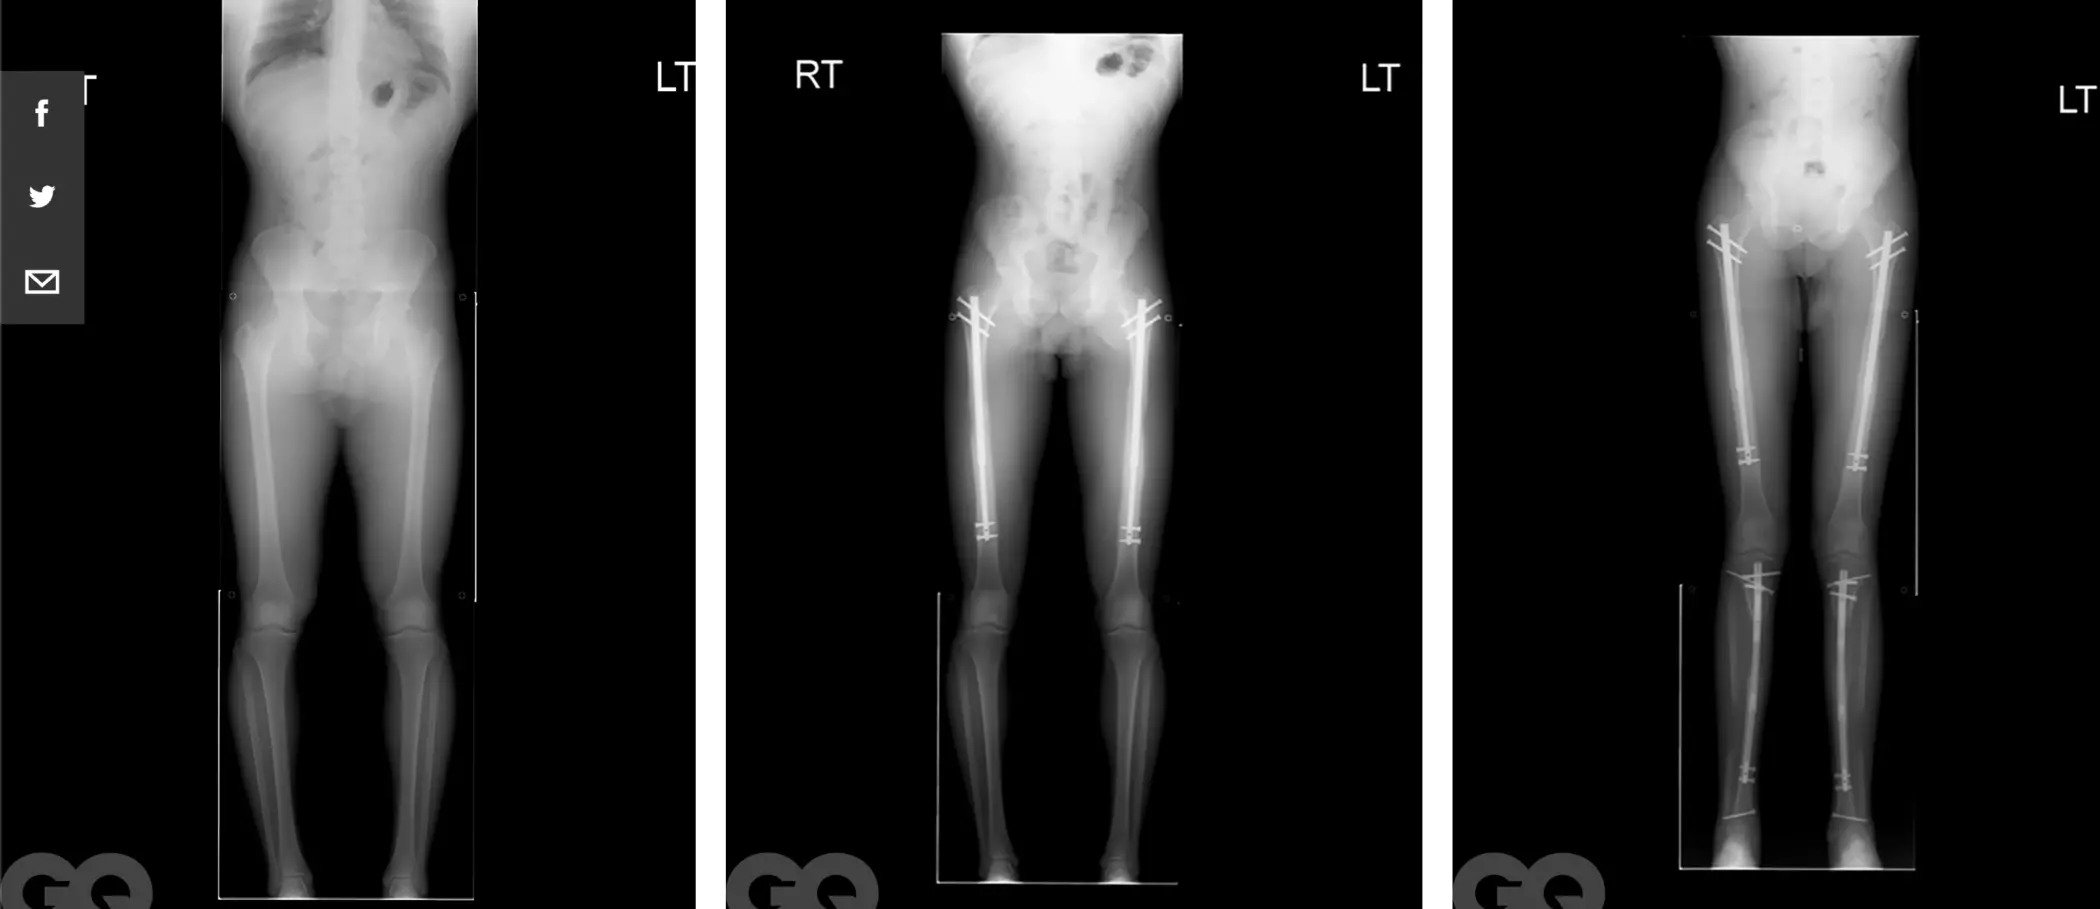

Проходит процедура следующим образом. Пациенту контролируемым образом ломают бедренные кости, а затем вставляют в них регулируемые металлические штыри. Затем с помощью магнитного пульта день за днем понемногу раздвигают штыри, увеличивая клиенту рост. Это крайне болезненный процесс, который занимает от 2 до 3-х месяцев. В течение этого времени нормально ходить на своих двоих – невозможно.

Рост, к слову, операция действительно увеличивает существенно, вплоть до 15 см, но заплатить за такой результат придется тоже немало — от 70 до 150 тысяч долларов. У человека, который давал интервью GQ, получилось подрасти со 167 до 175 сантиметров.